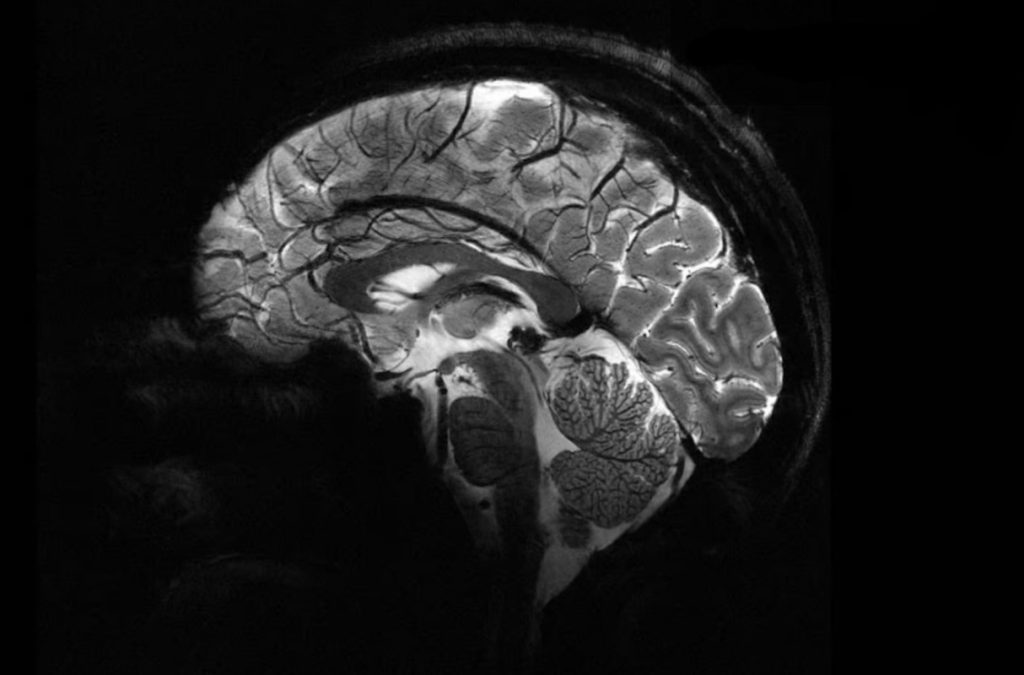

قدرتمندترین دستگاه MRI جهان اولین اسکن مغزی خیرهکننده را ثبت کرد. به گزارش رسانه مدیاتی، قدرتمندترین دستگاه MRI جهان با